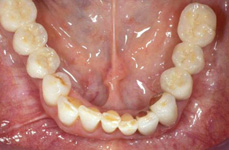

V případě chybění většího počtu zubů v postranních úsecích čelistí je možné ošetření pomocí implantátů, které nahradí ošetření pomocí snímacích náhrad kotvených na zbývajících zubech nebo patře.

Protetické řešení může být pomocí můstku, který je kotvený na implantátech nebo pomocí jednotlivých korunek na implantátech.

V zásadě je možné do těchto můstků zařadit i přirozené zuby, zejména pokud je potřeba tyto zuby ošetřit proteticky - korunkami. Korunky nebo můstky mohou být na implantáty nacementovány nebo přišroubovány.

Zdravé zuby zůstanou zachovány a přitom náhrady jsou pevné, jako na vlastních zubech